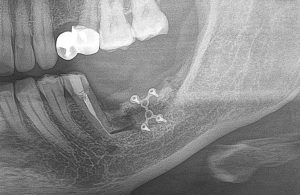

После операции:

— контрольный снимок (раньше делали ОПТГ, сейчас — строго КЛКТ)

Для этого мы сделали КЛКТ:

И КЛКТ показала нам, что с имплантатами и окружающей костью всё зашибись. Через 12 лет после операции, отсутствия наблюдения, пофигизма в замене временных коронок! Нужны ли тебе еще какие-нибудь доводы в пользу долгосрочной эффективности метода?